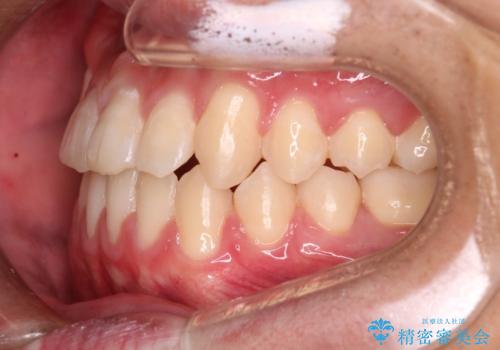

心配していた歯肉退縮も起こらず、前歯の噛み合わせと歯並びが綺麗に改善されました。

期間も1年2ヶ月と短期間で終了することができ、とても満足度の高い治療になりました。